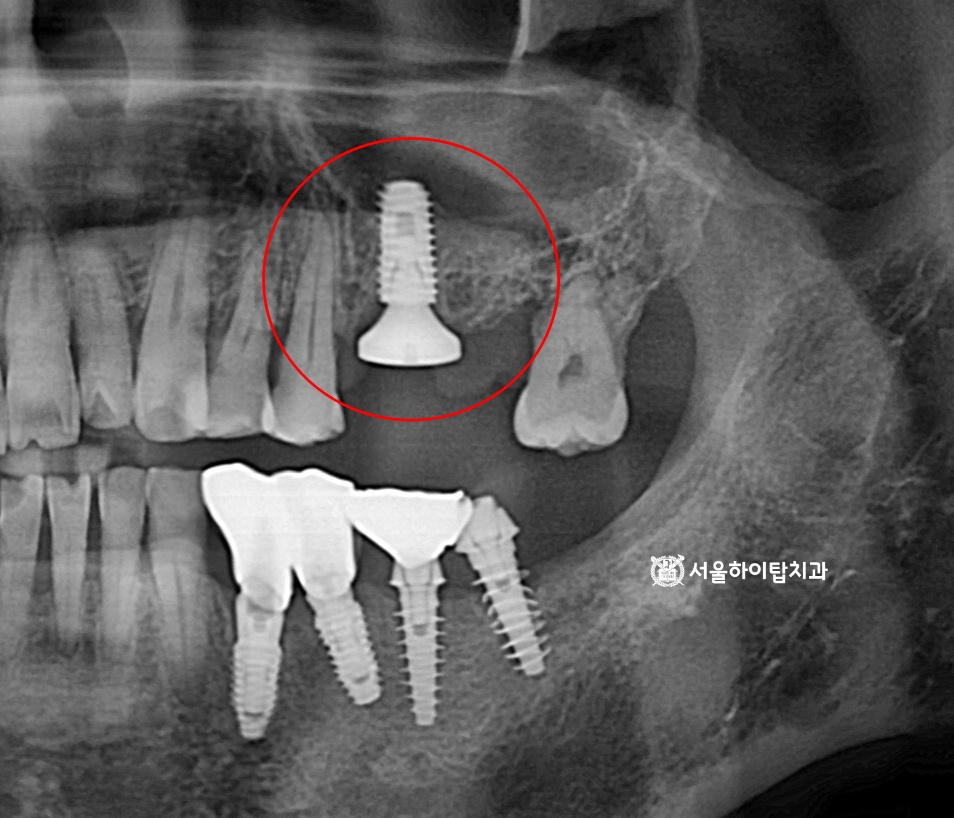

임플란트 Fixture 식립 완료

가상 시뮬레이션을 바탕으로, 임플란트가 알맞은 위치에 안전하게 식립된 모습입니다.

이후 약 2~3개월간의 골 유착 기간을 거치며,

뼈와 픽스처가 단단하게 결합되는 과정을 거치게 됩니다.

이 과정 중 약 한 달 정도가 지난 시점에, 다시 한 번 엑스레이 촬영을 시행하여

픽스처의 위치와 안정성, 그리고 초기 골 유착 상태를 확인하게 됩니다.

이를 통해 임플란트가 안정적으로 유지되고 있는지를 점검한 뒤,

이상 소견이 없다면 이후 보철 치료 단계로 치료를 이어가게 됩니다.